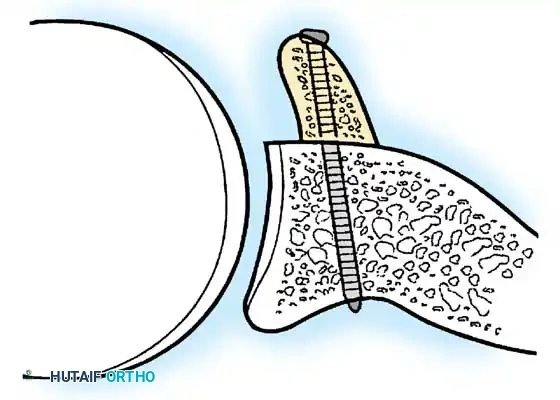

- Presence of glenoid bone loss (>15-20%) necessitating a coracoid transfer (Latarjet) or bone block.

- Anchor Placement: Suture anchors (typically 3 to 4) are placed along the articular margin of the anteroinferior glenoid (from the 5:30 to 3:00 positions for a right shoulder). Anchors must be inserted at a 45-degree angle to the articular surface to maximize pullout strength and avoid joint penetration.